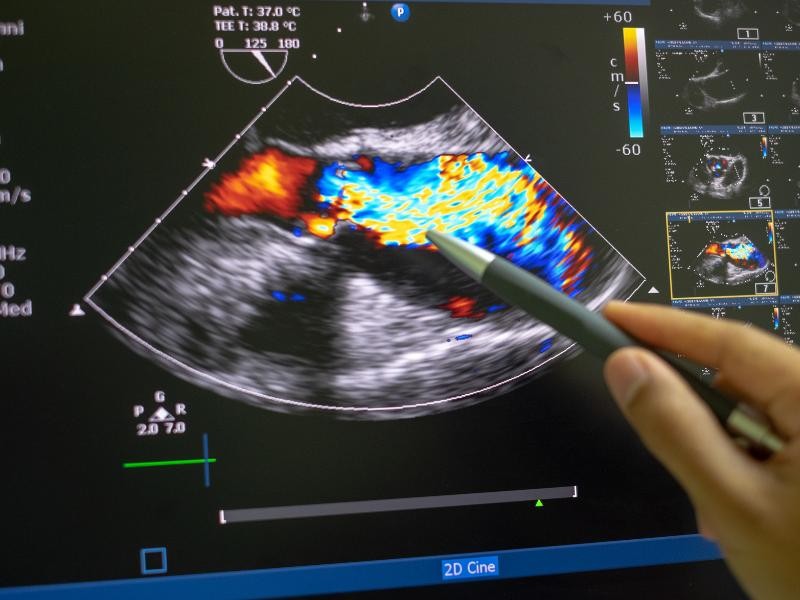

O Ultrassom Doppler da Aorta e Artérias Iliacas é um exame não invasivo e altamente preciso que utiliza ondas sonoras para avaliar a circulação sanguínea nas principais artérias do corpo, focando especialmente na aorta e nas artérias iliacas. Este exame combina a tecnologia do ultrassom com o efeito Doppler, permitindo a análise detalhada do fluxo sanguíneo, a identificação de possíveis obstruções, estreitamentos (estenoses), aneurismas e outras condições vasculares que possam afetar a saúde dessas importantes artérias. A Aorta, a maior artéria do corpo, e as Artérias Iliacas, que irrigam as extremidades inferiores, são fundamentais para o transporte de sangue para os órgãos e tecidos. Portanto, o Ultrassom Doppler da Aorta e Artérias Iliacas é essencial para a detecção precoce de problemas circulatórios graves, como aneurismas da aorta abdominal ou doença arterial periférica, garantindo um diagnóstico rápido e eficaz.

O Ultrassom Doppler da Aorta e Artérias Iliacas desempenha um papel vital na detecção de condições vasculares que podem ter consequências graves para a saúde. Esse exame é crucial para a identificação de aneurismas da aorta, que são dilatações anormais na parede da artéria, podendo ser fatais se não tratadas. Além disso, ele também auxilia na detecção de estenoses (estreitamentos) nas artérias iliacas, que podem levar a problemas circulatórios e insuficiência arterial, resultando em dor nas pernas, cãibras e até gangrena se não tratada. A monitorização da saúde vascular das artérias aórtica e iliaca com o exame Doppler oferece um método eficaz para diagnosticar a presença de doenças vasculares periféricas e arteriais de forma não invasiva. Detectar problemas precocemente por meio do Ultrassom Doppler da Aorta e Artérias Iliacas pode ser a chave para o tratamento precoce e prevenção de complicações graves, evitando intervenções mais invasivas no futuro.